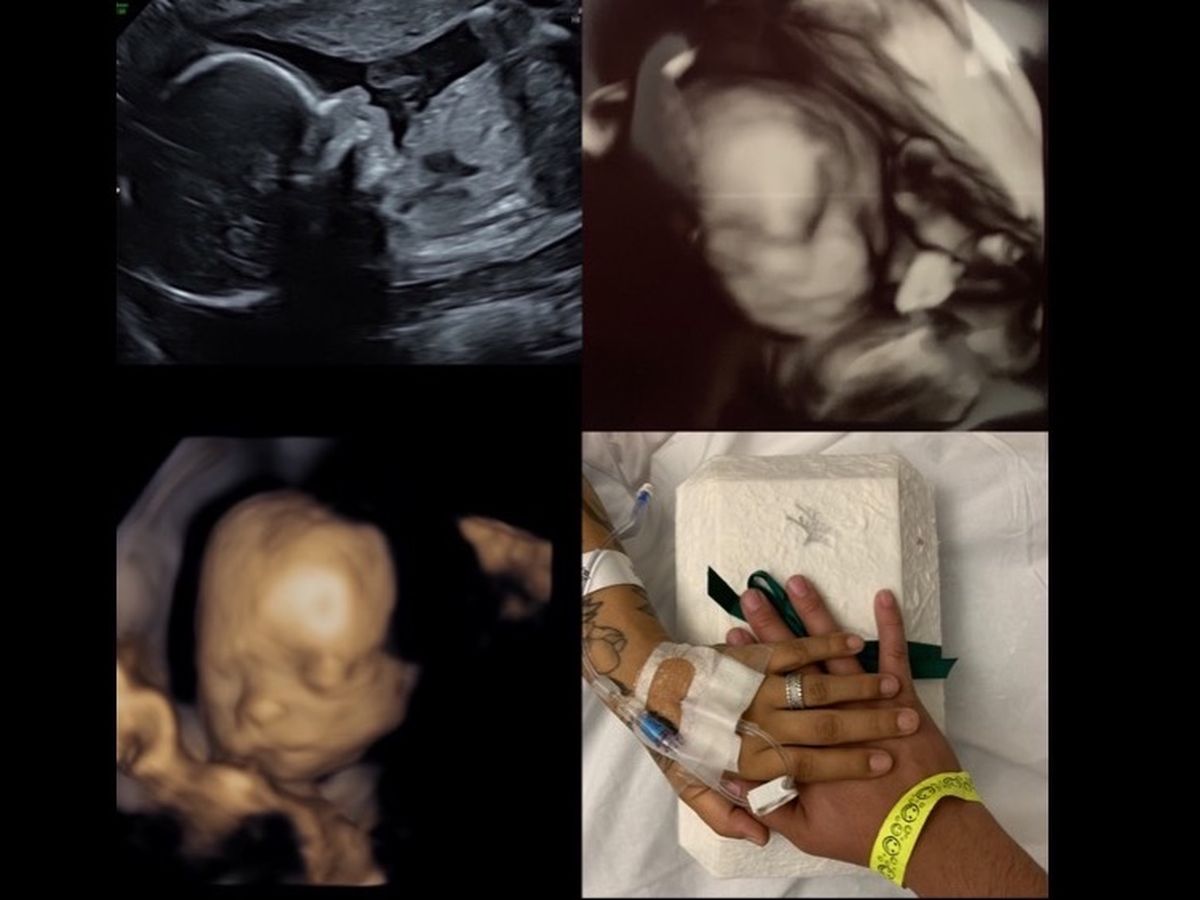

Our family has been so excited awaiting for my nieces arrival. It feels unbelievable that we had all gathered around listening to her heartbeat then to get news a couple days later Doctor couldn’t find her heartbeat anymore at only 6 months of life in her mommy’s tummy. It brings so much pain of how short her time was here on Earth.

This baby girl has been loved unconditionally since the moment we found out my sister was expecting. It is very unfortunate and a loss beyond words to have to say our goodbyes before we got an opportunity to welcome her home. Our baby girl came to earth with a God given mission to save her mommy’s life. We would have never known we could have lost our sister Marisol from a stroke without her having to go to the Doctor for her pregnancy. That’s when she was told she was at very high risk of a stroke due to high blood pressure. Without Baby Catalinas coming we could have lost our sister Marisol. Our perfect little angel Catalina has reminded us that this isn’t our forever home. Although, this is heartbreaking we have been able to welcome an angel. Our family finds closure that she experienced nothing but love while we awaited her arrival. My sister, Marlene, and I (Melissa)are asking for support to help our sister Marisol and her husband Richard cover the costs for their baby angel Catalina’s services. We deeply thank you all for your help in advance and may God bless you all.